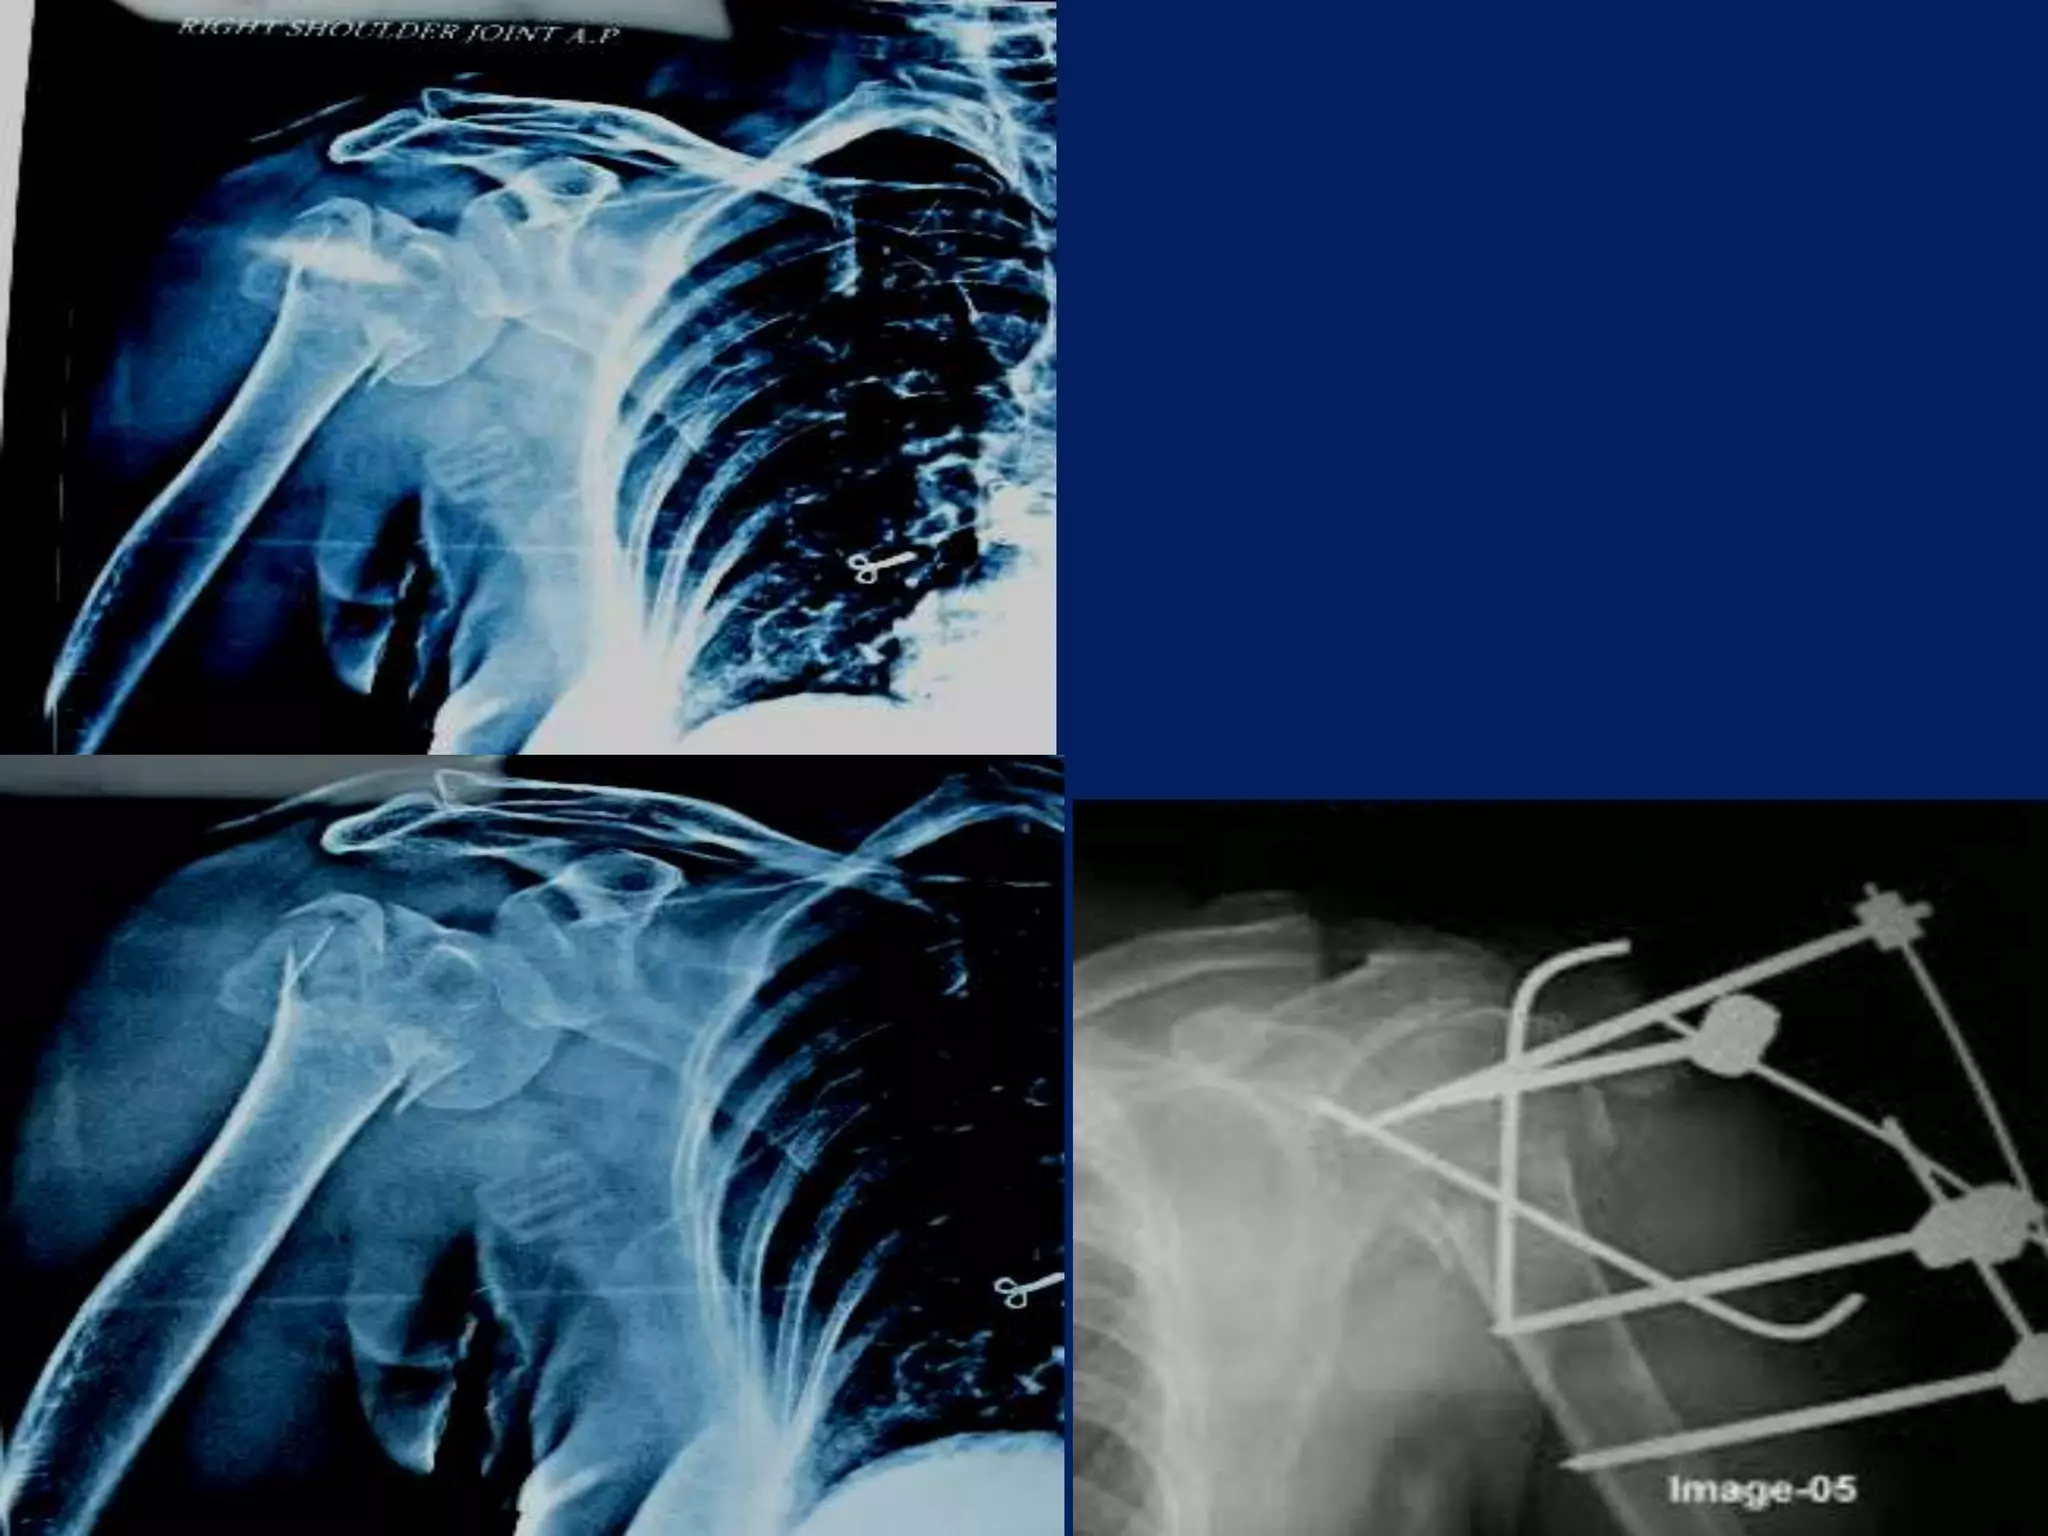

Fracture proximal humerus Fixation with K wires and External fixator